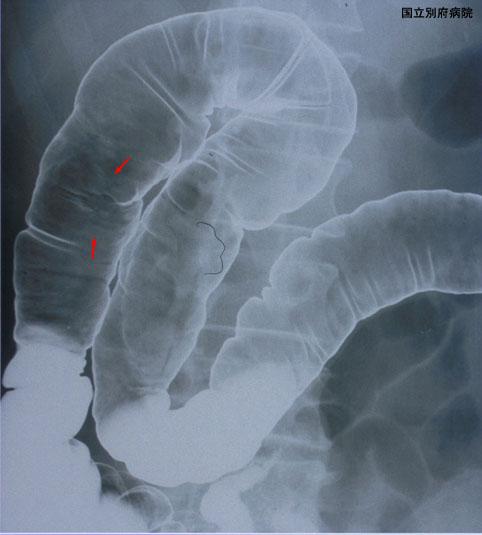

점막 주름의 집중을 동반한 IIc+ IIa형의 조기대장암(증례제시:국립 벳부병원)

[Image-ID:3091]

악성 상피성종양/선암

대장/상행

X-P

0형(표재형)/IIc형(IIc+IIa)

15~19

sm